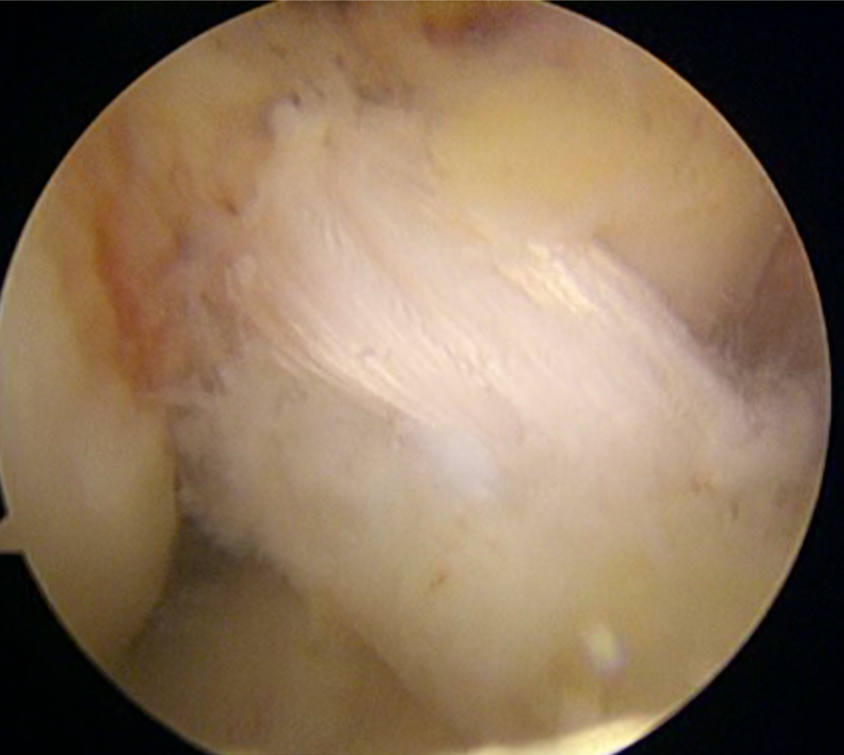

Reconstrucción De Ligamento Cruzado Anterior Por Artroscopia

Paquete de Cirugía: Reconstrucción de Ligamento Cruzado Anterior (LCA)

Equipo y material quirúrgico, incluyendo:

Torre de artroscopia

Insumos para realizar la reconstrucción del ligamento cruzado anterior (sin IVA)

Este paquete está diseñado para ofrecerte una cirugía minimamente invasiva, precisa y segura, enfocada en recuperar la estabilidad de tu rodilla, disminuir el dolor y ayudarte a regresar a tus actividades deportivas y de la vida diaria.